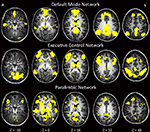

Network Maps

Complete network maps generated using three separate one-sample t-tests (Figure 1

Figure 1. Map of neural connectivity for the three major resting-state networks across all subjects (n = 38). p < 0.0001. Red circles denote approximate locations of seed-point ROIs.

Figure 2. One-sample t-tests within each genetic group depicting group effects for three major resting-state networks at p < 0.0001.